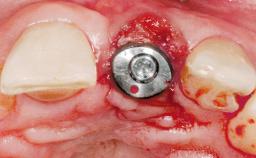

Late Placement of an Implant in a Maxillary Left Central Incisor Site

# of Implants 1

Type of Implants Two-Piece

Bone Augmentation Horizontal|Staged

Augmentation Materials Xenogenous|Membrane